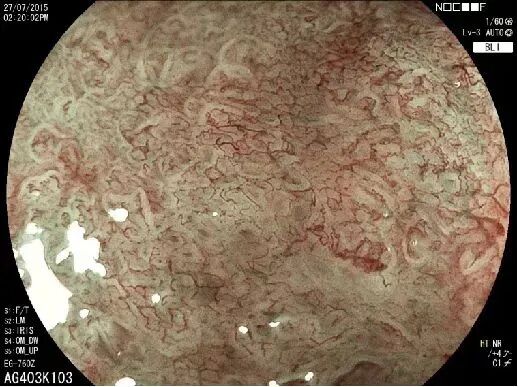

富士6000拥有超强高清的视图及LCI、BLI特殊光染色,能够详细观察粘膜表层微血管以及微结构,可以更全面、更快速的发现早癌及其他消化道病灶,有效提高消化道早期肿瘤病变和炎性疾病的检出率,让消化道早癌无处遁形。